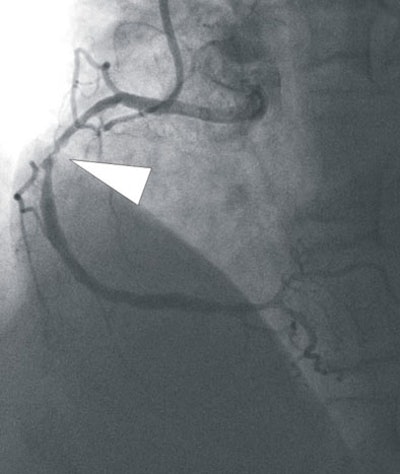

| In a 64-year-old man with chest pain, conventional catheter angiography confirmed the coronary CTA findings, and described a 50% ostial stenosis with diffuse disease throughout the vessel and a discrete 90% stenosis in the mid right circumflex artery (RCA) (arrows). |

The coronary CTA results revealed significant coronary artery stenosis (> 50%) in 16 of the 35 patients. Compared to conventional catheter-based angiography, coronary CTA had sensitivity of 98%, specificity of 88%, and accuracy of 92% for detecting coronary artery stenosis.